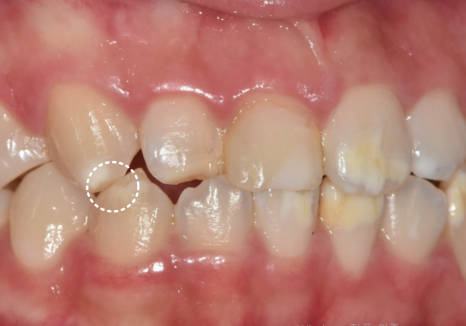

반점치 치료에서

가장 먼저 확인해야 할 부분은

얼마나 넓게 퍼져 있는지,

그리고 표면적인지 깊이가 있는지입니다.

앞니 한두 개에만 있는지,

앞니 전반에 퍼져 있는지에 따라

치료 선택이 달라질 수 있습니다.